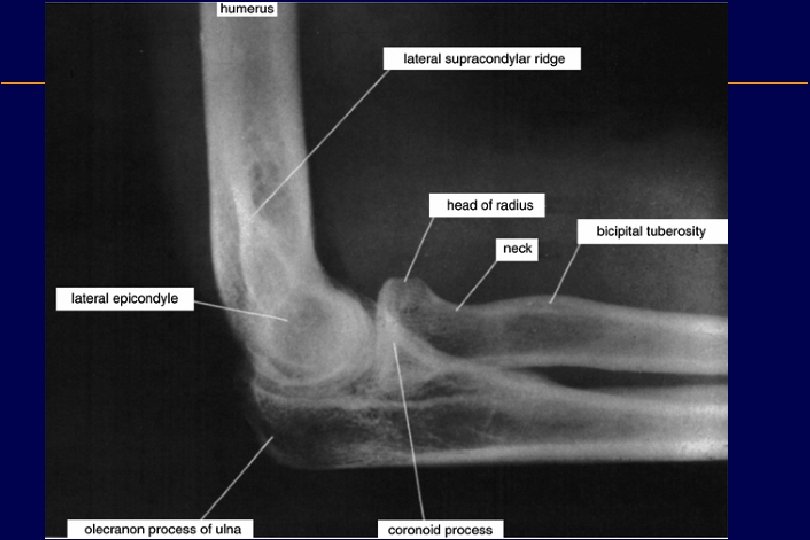

Distal Humerus • Medial epicondyle: – The pronator and flexor muscles of the forearm originate here • Lateral epicondyle: – The extensor and supinator muscles of the forearm originate here • Medial supracondylar ridge • Lateral supracondylar ridge • Trochlea (medial condyle): – Articulates with the trochlear notch of the ulna • Capitulum (lateral condyle): – Articulates with the radial head

Distal Humerus • Coronoid fossa: – Accommodates the coronoid process of the ulna during flexion. – A fat pad is situated here • Radial fossa: – Accommodates the head of the radius during flexion. – A fat pad is situated here • Olecranon fossa: – Accommodates the olecranon – A fat pad is situated here • Groove for ulnar nerve

Radius • The radius is the lateral and shorter of the two forearm bones. • Its proximal end consists of: 1. A short cylindrical (or thick disc like) head » The smooth superior aspect of the head of the radius is concave for articnlation with the capitulum of the hnmerus during flexion and extension of the elbow joint. » The head also articulates peripherally with the radial notch of the ulna » The head is covered with articular cartilage. 2. A neck » Relatively constricted between the head and the tuberosity. 3. A medially directed tuberosity » The oval radial tuberosity separates the proximal end of the radius from the body.

Ulna • The stabilizing bone of the forearm is the medial and longer of the two forearm bones • Its proximal end has two prominent projections: – The olecranon: » projects proximally from its posterior aspect – The coronoid process » Projects anteriorly.

The olecranon • The olecranon is the most proximal posterior eminence of the ulna • It is on the dorsal subcutaneous border and contains broad attachments for the triceps posteriorly • Anteriorly, the olecranon forms the trochlear notch of the ulna, which articulates with the trochlea • The radial notch – On the lateral side of the coronoid process is a smooth, rounded concavity, which articulates with the head of the radius.